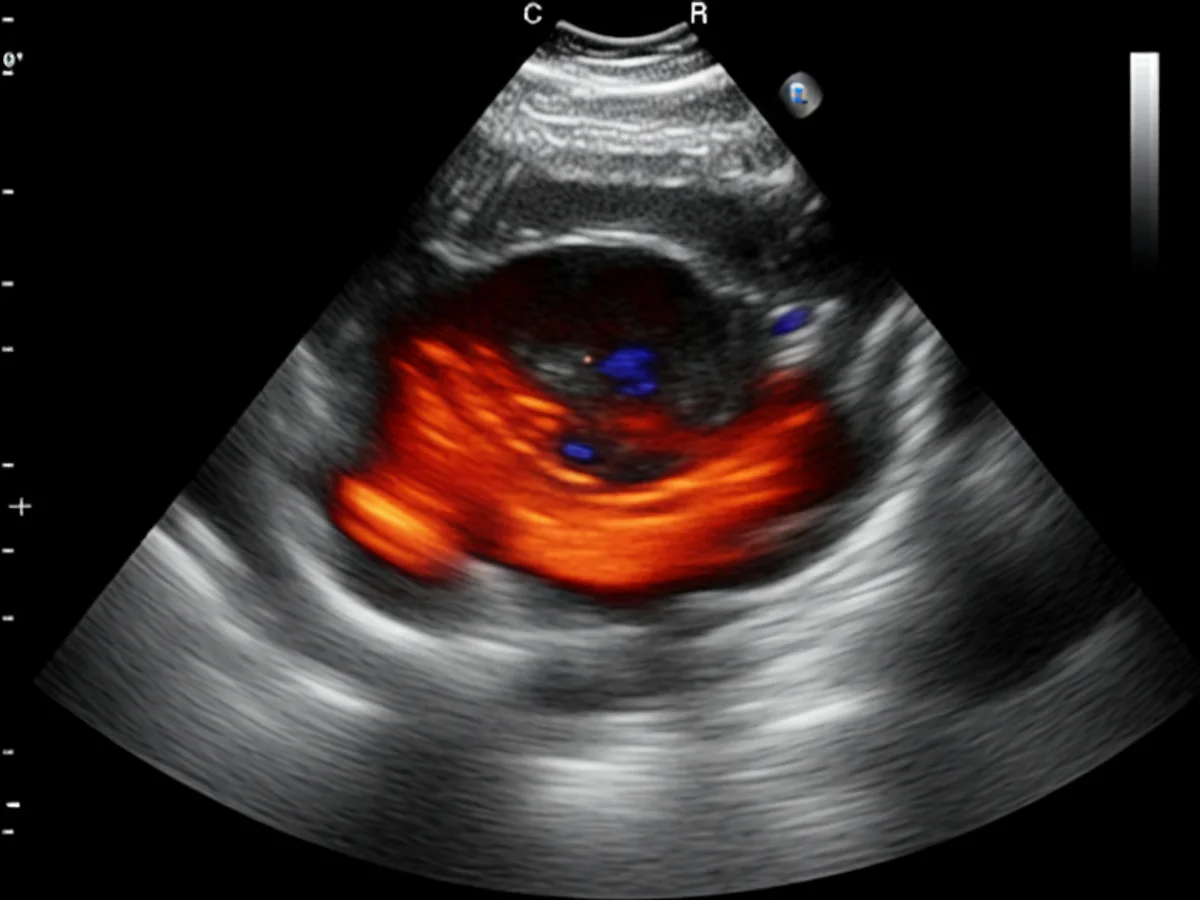

Zur Diagnose von Arthrose wird der Tierarzt zunächst eine gründliche körperliche Untersuchung Ihres Hundes durchführen, um den Bewegungsumfang und eventuelle Schmerzreaktionen zu beurteilen. Oft sind Röntgenaufnahmen erforderlich, um den Zustand der Gelenke genauer zu untersuchen. In einigen Fällen kann auch eine Ultraschalluntersuchung oder MRT notwendig sein. Diese Tests helfen, andere mögliche Ursachen für die Symptome auszuschließen und die Schwere der Arthrose zu bestimmen.